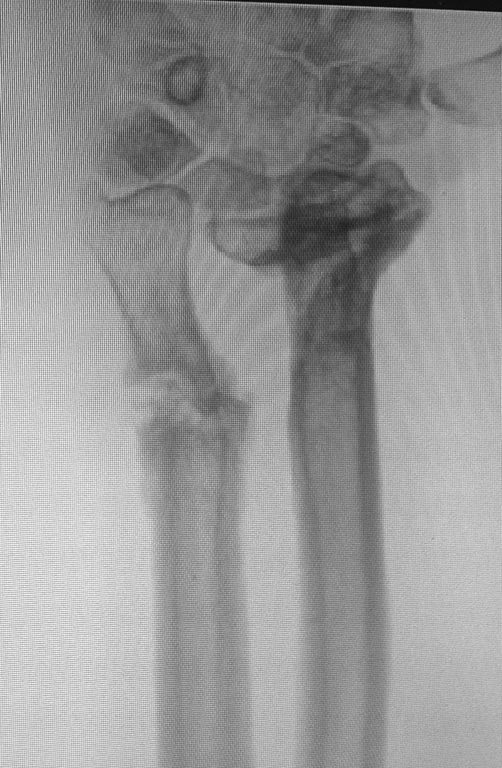

Предлагаю обсудить возможную тактику лечения пациента с деформацией

костей предплечья.

Пациент получил огнестрельное ранение левого предплечья с переломом

обеих костей в нижней трети в августе 2014г. Первоначально лечился в

аппарате Илизарова. Со слов пациента, в связи с развитием ИО в область

проведения спиц аппарат демонтирован, продолжено лечение в повязке. В

настоящее время в области левого предплечья множественные окрепшие

послеоперационные рубцы, отмечается деформация в виде выстояния головки

локтевой кости, формирования гипертрофической костной мозоли лучевой

кости. Рентгенограммы прилагаю.

Основная жалоба - ограничение супинации, которое мешает выполнять

работу. Прошу помочь в выборе тактики лечения. Спасибо.